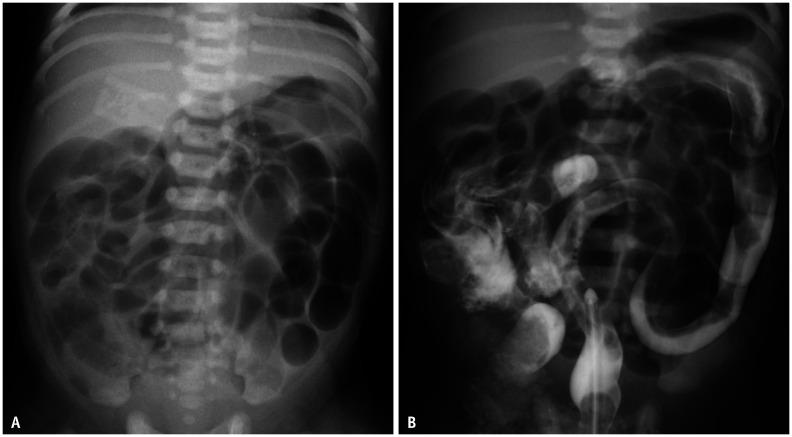

Gastrointestinal (GI) emergencies in neonates and infants encompass from the beginning to the end of the GI tract. Both congenital and acquired conditions can cause various GI emergencies in neonates and infants. Given the overlapping or nonspecific clinical findings of many different neonatal and infantile GI emergencies and the unique characteristics of this age group, appropriate imaging is key to accurate and timely diagnosis while avoiding unnecessary radiation hazard and medical costs. In this paper, we discuss the radiological findings of essential neonatal and infantile GI emergencies, including esophageal atresia and tracheoesophageal fistula, hypertrophic pyloric stenosis, duodenal atresia, malrotation, midgut volvulus for upper GI emergencies, and jejunoileal atresia, meconium ileus, meconium plug syndrome, meconium peritonitis, Hirschsprung disease, anorectal malformation, necrotizing enterocolitis, and intussusception for lower GI emergencies.

新生儿和婴儿的胃肠道(GI)急症涵盖了从胃肠道的开始到结束的各个方面。先天性和后天性疾病都可能导致新生儿和婴儿出现各种胃肠道急症。鉴于许多不同的新生儿和婴儿胃肠道急症的临床发现具有重叠或非特异性,以及该年龄段的独特特征,适当的影像学检查对于准确和及时的诊断至关重要,同时避免不必要的辐射危害和医疗费用。在本文中,我们讨论了基本的新生儿和婴儿胃肠道急症的放射学表现,包括食管闭锁和食管气管瘘、肥厚性幽门狭窄、十二指肠闭锁、肠旋转不良、胃上消化道急症,以及空肠回肠闭锁、胎粪性肠梗阻、胎粪栓综合征、胎粪性腹膜炎、先天性巨结肠、肛门直肠畸形、坏死性小肠结肠炎和肠套叠等下消化道急症。